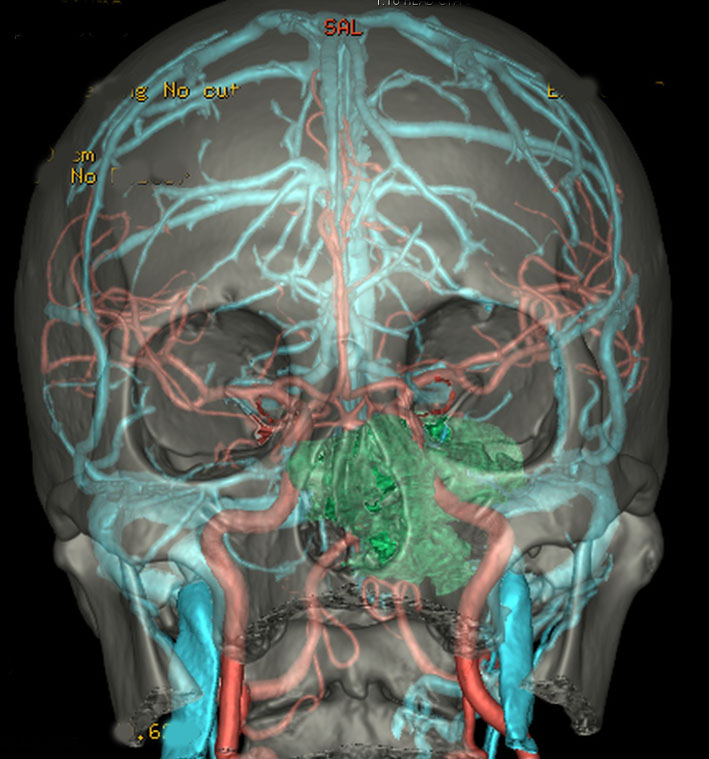

左動眼神経麻痺が急速に進行した例です。斜台から左海綿静脈洞,錐体骨尖を侵す頭蓋底軟骨肉腫です。左内頚動脈は腫瘍に取り囲まれています。

グレード2の軟骨肉腫でした。軟骨肉腫は軟らかい腫瘍です。もちろん頭蓋底骨に浸潤しているので全摘出は無理ですが,大部分を摘出して術後に放射線治療をするのが標準的な治療です。ガンマ線による放射線治療でもコントロールできることは多いでしょう。逆に,重粒子線(炭素線)などの治療は侵襲的過ぎます。